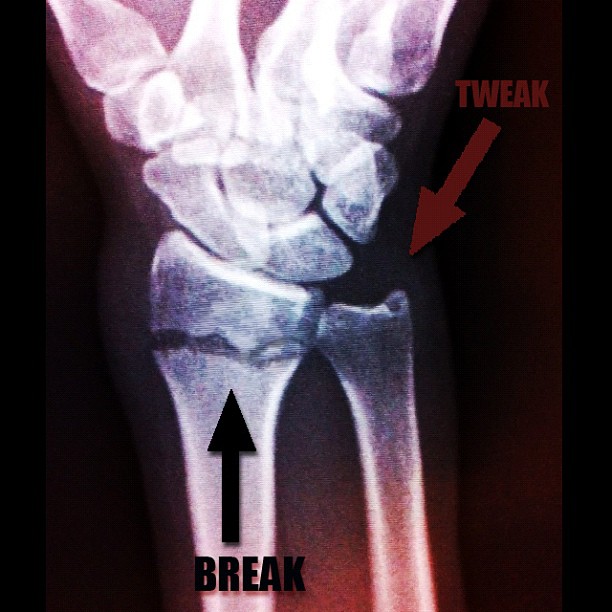

Yep … it’s definitely broke! Here’s a photo of my wrist AFTER I slammed it back in place .. sort of in place at least. :-\